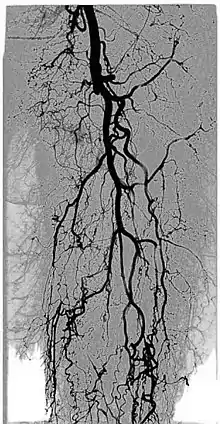

Digital variance angiography (DVA)

See also: Digital variance angiography

The diagnostic value of radiographic images is limited by image quality, which can be measured through signal-to-noise ratio (SNR) calculations. The higher the value of SNR, the better the image. The SNR can be increased initially by enhancing the "signal" or "contrast", which is the intensity difference between the object of interest and the background. This is usually done by adding contrast medium to increase the attenuation values of the object, while holding the background values constant.[1][2][3][4]

By allowing visualization of movements, kinetic imaging offers a new type of motion-based contrast. In many cases, the kinetic image will have a higher SNR (better image quality) compared to traditional images for moving objects.[2][6][1][3][4]

This improvement in SNR and image quality has been studied by Gyánó M. et al. (2018)[3] and Óriás V. et al.(2019)[4] in the field of traditional angiographic imaging and carbon-dioxide imaging. Their findings indicate that by using the kinetic imaging (or as they called this method in the case of angiographies, digital variance angiograpy, DVA) for processing angiographic image sequences, the quality improvement may increase diagnostic insight and it also creates a quality reserve, which means that DVA could provide the same level of image quality, as the gold-standard DSA technique, but the dose of administered radiation and/or contrast agent could be lowered.[3]

Functional imaging

The kinetic image may allow visualisation of physiological movements, such as pulsing of the aorta, passing of a contrast agent bolus in the arteries, movement of the thoracic diaphragm, inflation and deflation of the alveoli in the lungs, or the constantly moving gastrointestinal tract.